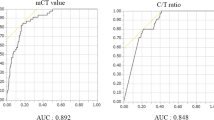

Statistical analysis

Multivariate logistic regression analysis was performed to identify the diagnosis effect of the 6 CT features (shape, spiculated sign, cavity, pleural indentation, bronchovascular convergence sign and lymphadenectasis) with statistical significance. It had a tendency toward PSCLC diagnosis with the CT features of lymphadenectasis and multinodular shape (P < 0.05); however, irregular shape, spiculated sign, cavity and pleural indentation sign had a higher tendency toward PNSCLC diagnosis (P < 0.05). In order to facilitate the clinical application, we set up a mathematical model based on the results of two logistic regression analyses, multiplied the β-coefficients of the significant CT feature by 10 and rounded to the nearest integer for analysis (Table 2). The scores of each CT feature were added together to get the final score of each patient, and we then obtained a group of continuous variables with a score of −51 to 23. The final score was chosen as variable, and the pathological diagnosis as the dependent variable (1 = PSCLC, 0 = PNSCLC), using the statistical software MedCalc to draw the ROC curve (Fig. 2); the AUC was 0.834 (95%CI 0.783–0.877). The maximum value of the Youden index was 0.5584, which corresponded to the most reasonable cut-off of −24. When the final score was more than −24, the diagnosis was PSCLC, and the sensitivity and specificity were 86.3% (95%CI 0.737−0.943) and 69.6% (95%CI 0.628−0.758), respectively.

The image scoring system model converted the CT features of peripheral lung cancer to qualitative data through logistic regression and ROC curve analysis (Table 2). When the final score was more than −24, the diagnosis was PSCLC, and the sensitivity and specificity were 86.3 and 69.6%, respectively. The AUC was 0.834, indicating that the accuracy of the diagnosis was moderate.